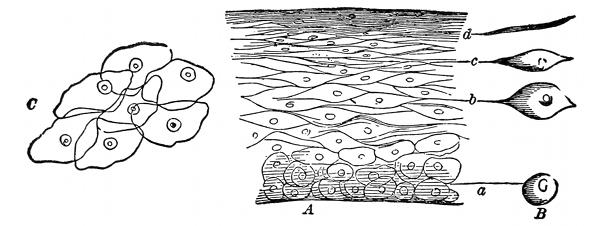

Fig. 1—A, A vertical section of the cuticle; B, the lateral view of the

cells; C, the flat side of scales like (d) magnified

250 diameters.